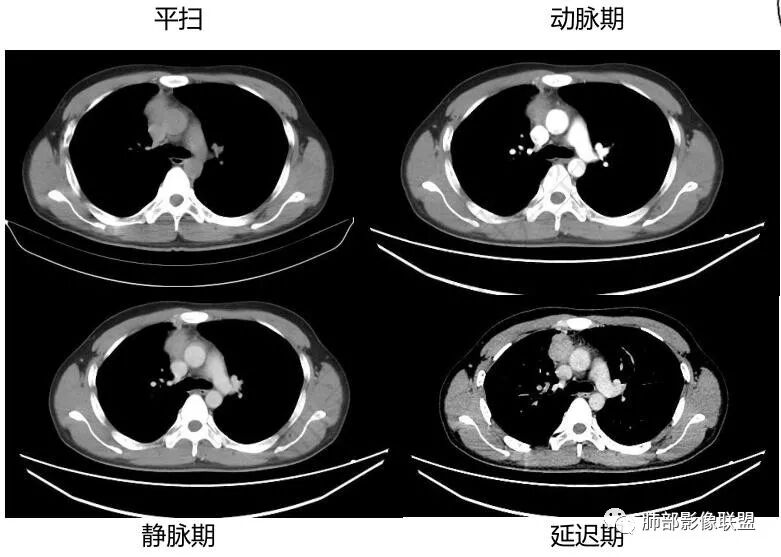

中青年男性,前纵膈偏右侧软组织肿块,形态不规则,有分叶,密度均匀,增强病灶轻中度强化,内部可见低或无强化区域,病灶与血管周围间隙分界不清晰,考虑恶性或交界性肿瘤,胸腺类癌>生殖细胞瘤>淋巴瘤。

青年男性,前上纵隔占位,渐进强化,坏死不明显,nse稍高,首先考虑类癌,鉴别精原,内胚窦瘤,需要结合实验室检查HCG,AFP等

中年男性,胸痛,既往健康,前上纵隔软组织肿块,形态不规则,密度不均,没有血管包埋及受侵征象,呈不均匀强化,考虑胸腺瘤,鉴别淋巴瘤,精原细胞瘤,胸腺癌

前纵隔右侧见大肿块,边缘清,同侧内乳动脉增粗,渐进性延迟强化明显,强化密度不均匀,中心见偏低密度灶,上腔静脉内后侧推压移位(提示肿块质地偏硬),副神经节瘤,与巨淋巴细胞增生症鉴别。

青年男性,咳嗽,右上前纵隔不规则肿块,分叶,上腔静脉受压,内乳动脉增粗,延迟强化明显,坏死不明显,考虑来源纵隔,胸腺瘤,淋巴瘤,神经源性肿瘤都可以,比较年轻,猜个淋巴瘤吧。神经源性肿瘤代排。

青年男性,前纵隔软组织肿块,偏右侧生长,边缘多发分叶,包绕临近血管生长,增强后轻度强化,并呈渐进性,可见点状坏死,考虑胸腺瘤,鉴别淋巴瘤,生殖细胞肿瘤,巨淋巴结增生症

青年男性,前纵隔偏右侧软组织肿块,密度均匀,分叶,渐进性不均匀强化,可见点状坏死,考虑胸腺瘤,鉴别生殖细胞肿瘤,淋巴瘤,CD。

青年男性,前纵隔偏右侧肿块,分叶,与邻近血管分界不清,上腔静脉受压,不均匀渐进强化,点状坏死,考虑胸腺瘤,鉴别胸腺类癌

男性32岁前纵隔偏右侧见一不规则软组织影,边缘毛刺,呈分叶征,同侧内乳动脉增粗,延迟性强化,内见条状分隔影,考虑胸腺瘤(B1、2,临界年龄段,分隔有些提示倾向),NSE轻度升高,中度强化,类癌代排。内胚窦及精原等生殖细胞肿瘤影像不符合,建议结合实验室检查

年轻男性,NSE稍高,前纵隔偏右侧不规则实性肿块,平扫密度均匀,增强渐进性不均匀强化,内见低密度区,似见条样分隔。考虑为胸腺瘤,建议实验室检查HCG,AFP等鉴别生殖细胞肿瘤

青年男性,前上纵隔占位,偏侧生长,边缘不规则,可见分叶及分隔,内见少量无强化低密度区,常规考虑胸腺瘤,NSE稍偏高一点,会不会是实验室误差?

前纵隔右侧不规则软组织肿块,边缘欠清,增强渐进性强化,内见星状无强化分隔,部分分隔延迟强化,青年男性,首先考虑精原细胞瘤,鉴别胸腺瘤,NSE轻度升高,类癌也需鉴别!

前纵隔肿块,轻度分叶,边界不清楚,延迟强化,可见分隔,倾向恶性或具有一定侵袭性病灶。